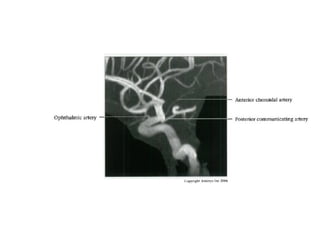

Multidetector CT angiogram depicts a hyperplastic anterior choroidal

artery (straight arrow), ipsilateral posterior communicating artery

(arrowhead), and contralateral fetal posterior cerebral artery (curved

arrow).

RadioGraphics 2009; 29:1027–1043